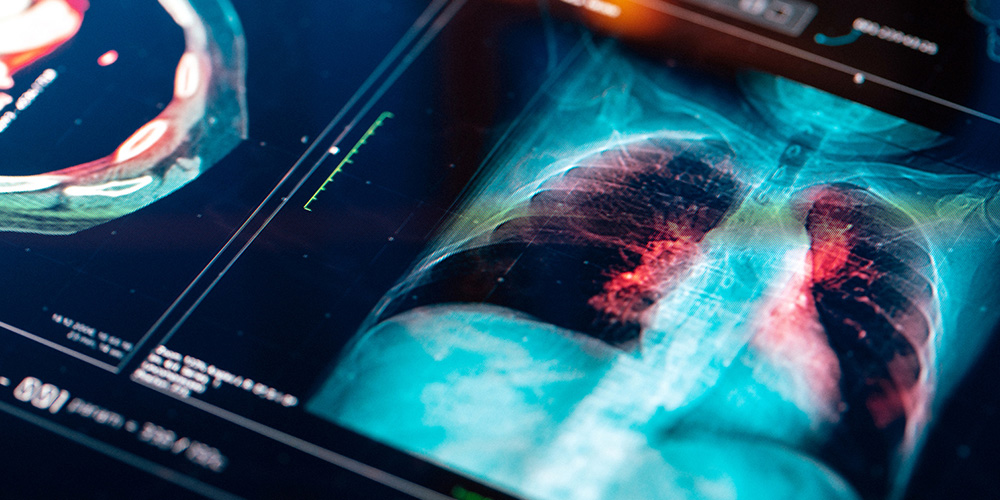

The Khaled Hassan lab is studying lung cancer development and progression as well as mechanisms of resistance to its treatment.